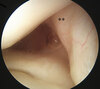

Arthroscopic image of a knee shows the posterior cruciate ligament bundle origins. The anterolateral bundle (ALB) and the posteromedial bundle (PMB) are observed at their origin on the lateral side of the medial femoral condyle (MFC), or the medial intercondylar notch.